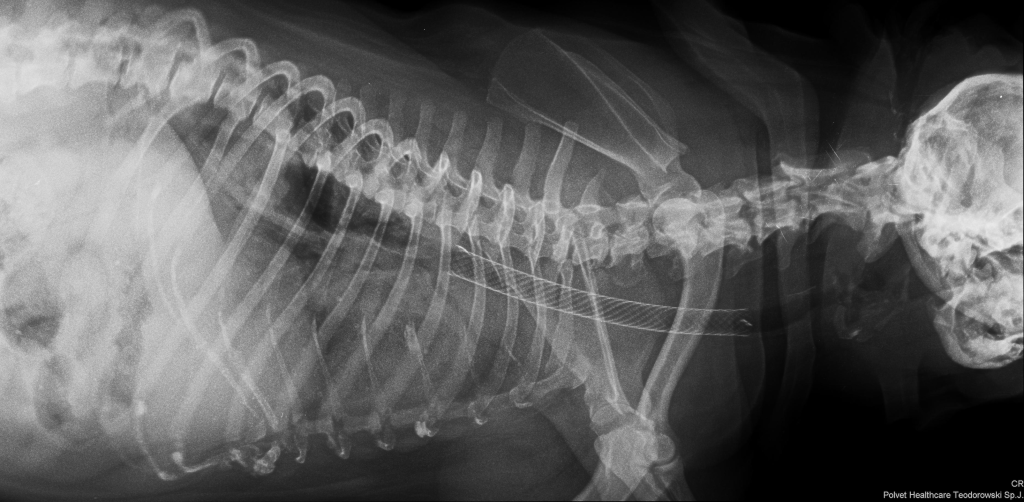

Stenty w leczeniu zwężenia tchawicy

Jednym z częstszych zastosowań stentów w medycynie weterynaryjnej jest leczenie zapadania się tchawicy (collapsus tracheae). Schorzenie to powoduje zwężenie światła tchawicy, co prowadzi do kaszlu i trudności w oddychaniu.

Wprowadzenie stentu do tchawicy stabilizuje jej ściany i umożliwia swobodniejszy przepływ powietrza.

Zakładanie stentu wykonywane jest zazwyczaj pod kontrolą diagnostyki obrazowej, takiej jak fluoroskopia, tomografia komputerowa lub endoskopia. Pozwala to na precyzyjne umieszczenie implantu w odpowiednim miejscu.

Procedura przeprowadzana jest w znieczuleniu ogólnym i zwykle wymaga krótszego czasu rekonwalescencji niż klasyczna operacja chirurgiczna.